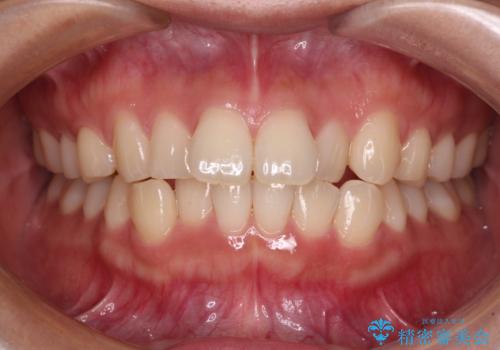

- 上下前歯のデコボコを気にして来院された患者様です。

ワイヤー矯正でもインビザラインでも、どの装置でも対応可能でしたが、安価で楽して素早く治療を終えたいとのことで、メタルブラケット装置による矯正治療を行うこととしました。